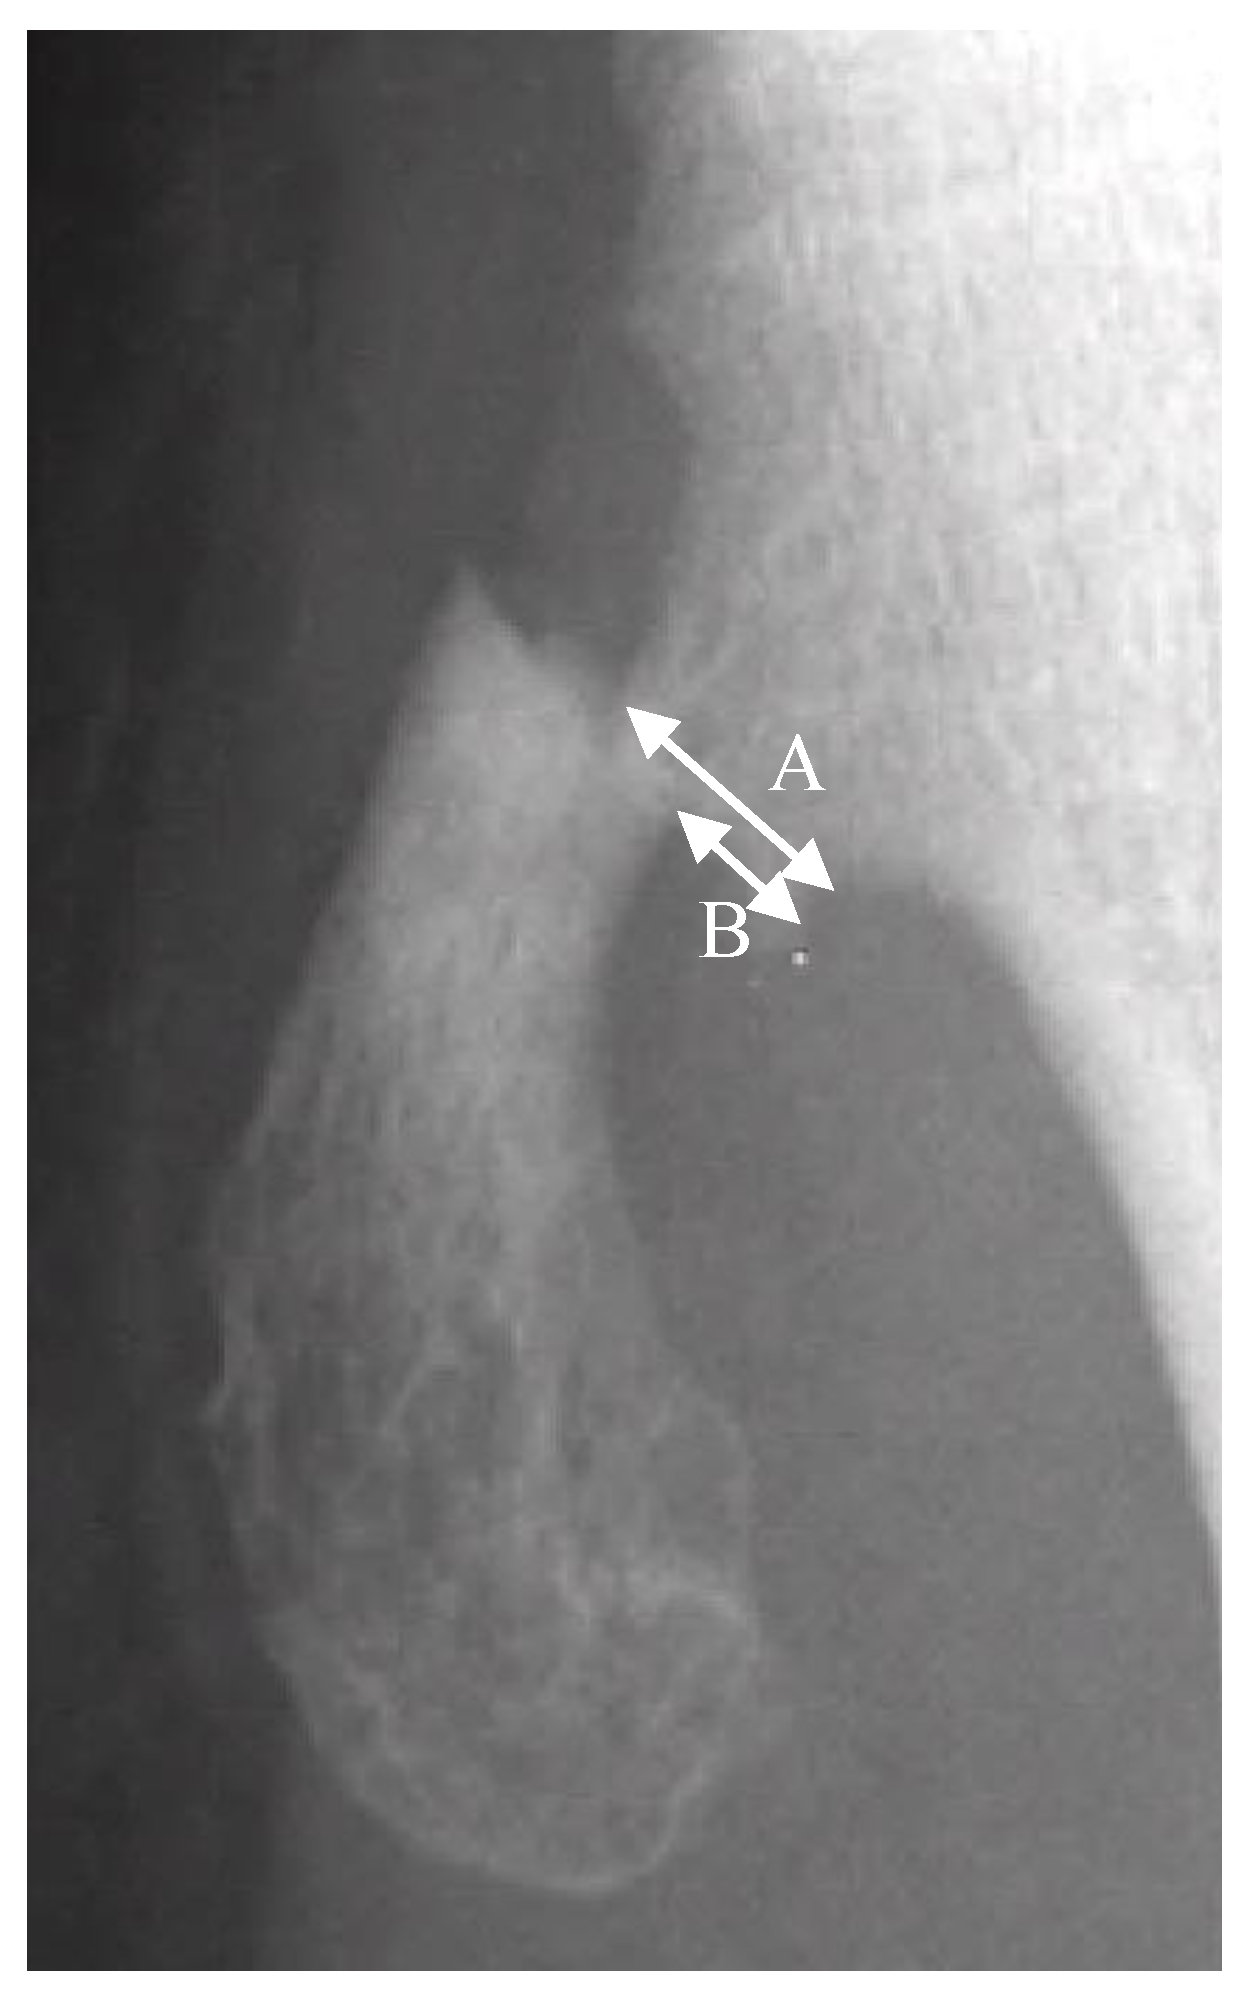

The fractures of the osteochondromas were divided into two types: displacement and non-displacement. In the present study, displacement was defined as a gap widening of more than 1 mm between fragments, or translation of more than 50% of the distal fragment in relation to the proximal fragment, either by anteroposterior, lateral, or oblique radiographic views of the knee joint (Figure 1). There were 12 patients in the displacement group and 11 patients in the non-displacement group (Figure 2).

Figure 1.

A is the width of the proximal fragment of the fractured osteochondroma. B is the displaced distance of the distal fragment in relation to the proximal fragment. Translation is defined by the equation of B/A × 100%.